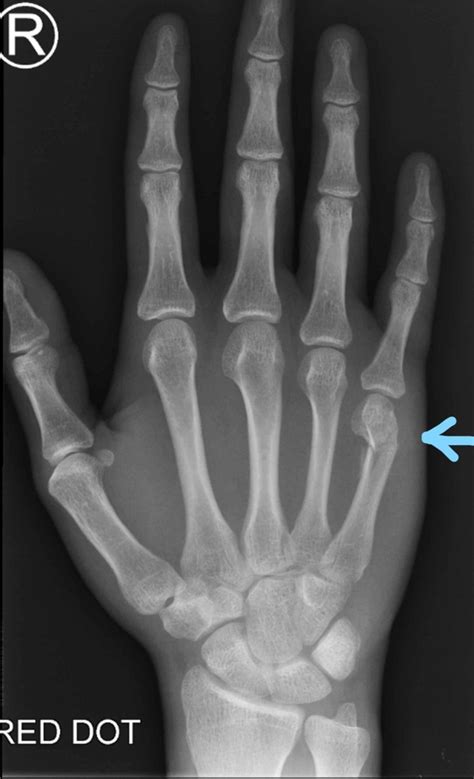

• boxer's fracture treatment at home

• what is a boxer's fracture

• boxer fracture healed incorrectly

• boxer fracture treatment protocol

• closed boxer's fracture

• boxers hand fracture recovery time